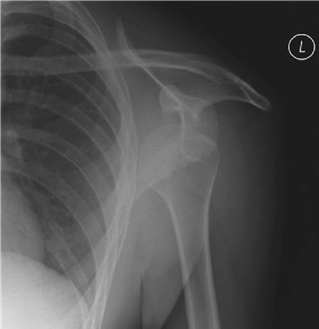

Describe the radiograph. What is your diagnosis?

T his is an AP view of the right shoulder showing a deformed humeral head with loss of joint space and subchondral sclerosis. This is osteoarthritis with a degree of avascular necrosis.